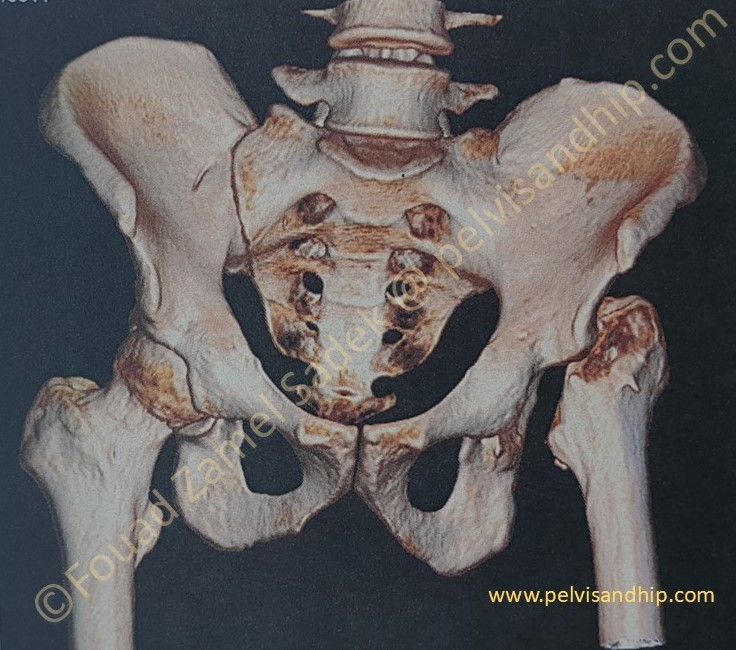

The 3D reconstruction is a very valuable tool for acetabular reconstruction planning. The left SI joint is obviously ankylosed. The anterior wall of the left acetabulum is quite sufficient with no deficiency. The projection of the posterior wall (which is visible in this view due to the absence of the femoral head) can be seen to have some slight deficiency. The upward migration of the left femur is also obvious and may represent some surgical challenges to bring the down the centre of rotation of the reconstructed hip.

The oblique view of the this 3D reconstruction again confirms the left SI joint ankylosis. It also brings in profile the superior dome which shows its deficiency.

The posterior view of the 3D reconstruction confirms again the posterior wall deficiency by comparison to the contralateral right hip posterior wall.